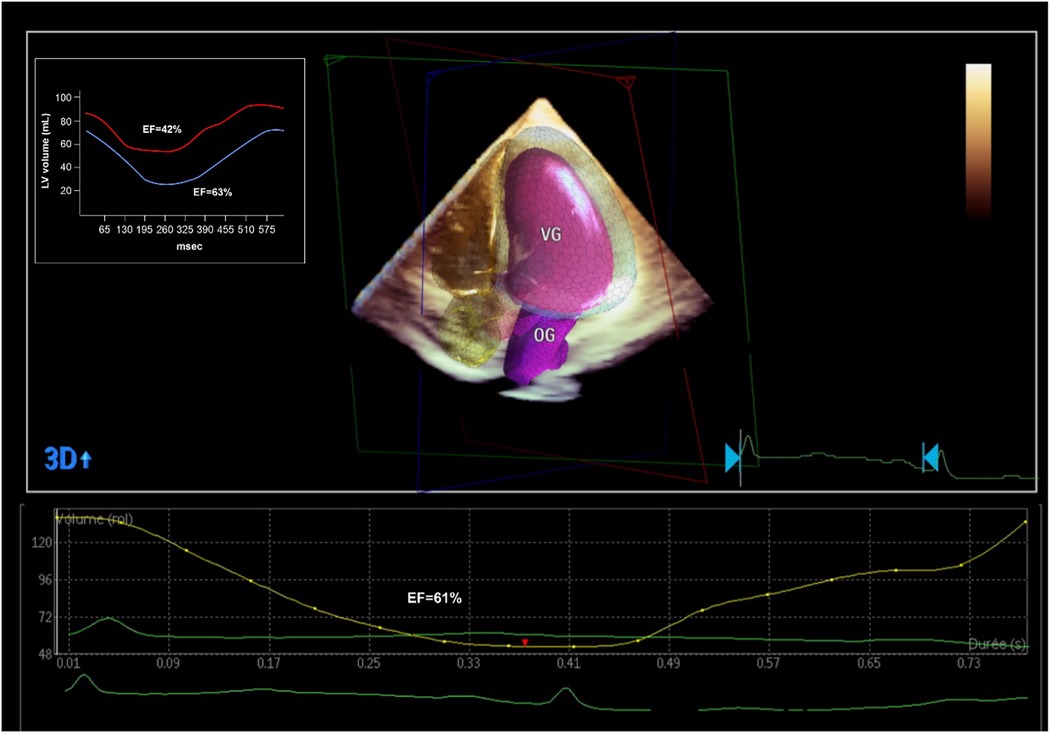

A TTE at day 5 showed complete recovery of the LVEF without any regional abnormalities (Figure 3).

Figure 3

Echocardiographic and PET-CT evaluation of the LVEF after the coronary revascularization. PET-CT showed a significant improvement in LVEF (from 42% to 63%) with a significant decrease globally in LV volumes, denoting an ischemic LV dilatation. 3D echocardiographic evaluation confirmed the normalization of the LVEF.

Myocardial ischemia is a key factor for guiding revascularization strategy in patients with stable coronary artery disease (2). The role of myocardial viability, though, is less clear. Historically, many observational studies and meta-analyses have suggested that in patients with dysfunctional myocardium, revascularization is associated with better outcomes and improved ventricular recovery when myocardial viability has been proven by advanced imaging (3). However, more recent controlled trials (STICH and REVIVED-BCI2) showed no benefit in survival with revascularization compared to optimal medical treatment in patients with decreased LVEF despite preserved myocardial viability (4, 5). These findings do not apply in acute, complex cases where viability may help differentiate hibernating myocardium from scar. This is extremely relevant for predicting segmental functional recovery after revascularization in the acute setting, even if this does not translate into improved clinical outcomes in the general population (6). However, this information is rarely available in the context of acute coronary syndromes. In this case, the patient presented to the emergency room with chest pain and ECG signs of diffuse myocardial ischemia. The urgent coronary angiography confirmed the presence of a severe 2-vessel disease involving the distal LM, proximal LAD, and LCX arteries. This was suspected after the initial 82-Rubidium PET-CT scan showing a massive, severe non-reversible perfusion defect covering the anterior, lateral, septal, and apical walls of the left ventricle (Figure 1). Although the LAD lesion was the culprit lesion for the acute coronary syndrome and ECG manifestations of ischemia, the LCX artery was found occluded with morphological aspects pointing to chronic total occlusion (CTO). Typically, in this case without information on the viability of the lateral wall, a recanalization of the LCX artery may not have been attempted, considering the technical challenge. However, the readily available viability test encouraged the operator to attempt the recanalization of the occluded LCX artery in an attempt to prevent further myocardial damage (7). The 18F-FDG viability test performed a few hours before the angiography, confirmed the presence of enhanced glucose metabolism in this area, which denotes a preserved viability of the myocardial cells, thus pointing to the presence of hibernating myocardium and not a scar. This information favored the prompt attempt for the recanalization of the LCX CTO at the time of the treatment of the culprit lesion (LM-LAD). This decision possibly explains the excellent short and mid-term results of the intervention, with the very rapid (in a few hours) restoration of the hemodynamic stability (ablation of the Impella CP system®), the normalization of the LVEF (62% vs. 40%, Figure 3) and the absence of significant myocardial defect at the latest perfusion PET-CT scan (Figure 4).